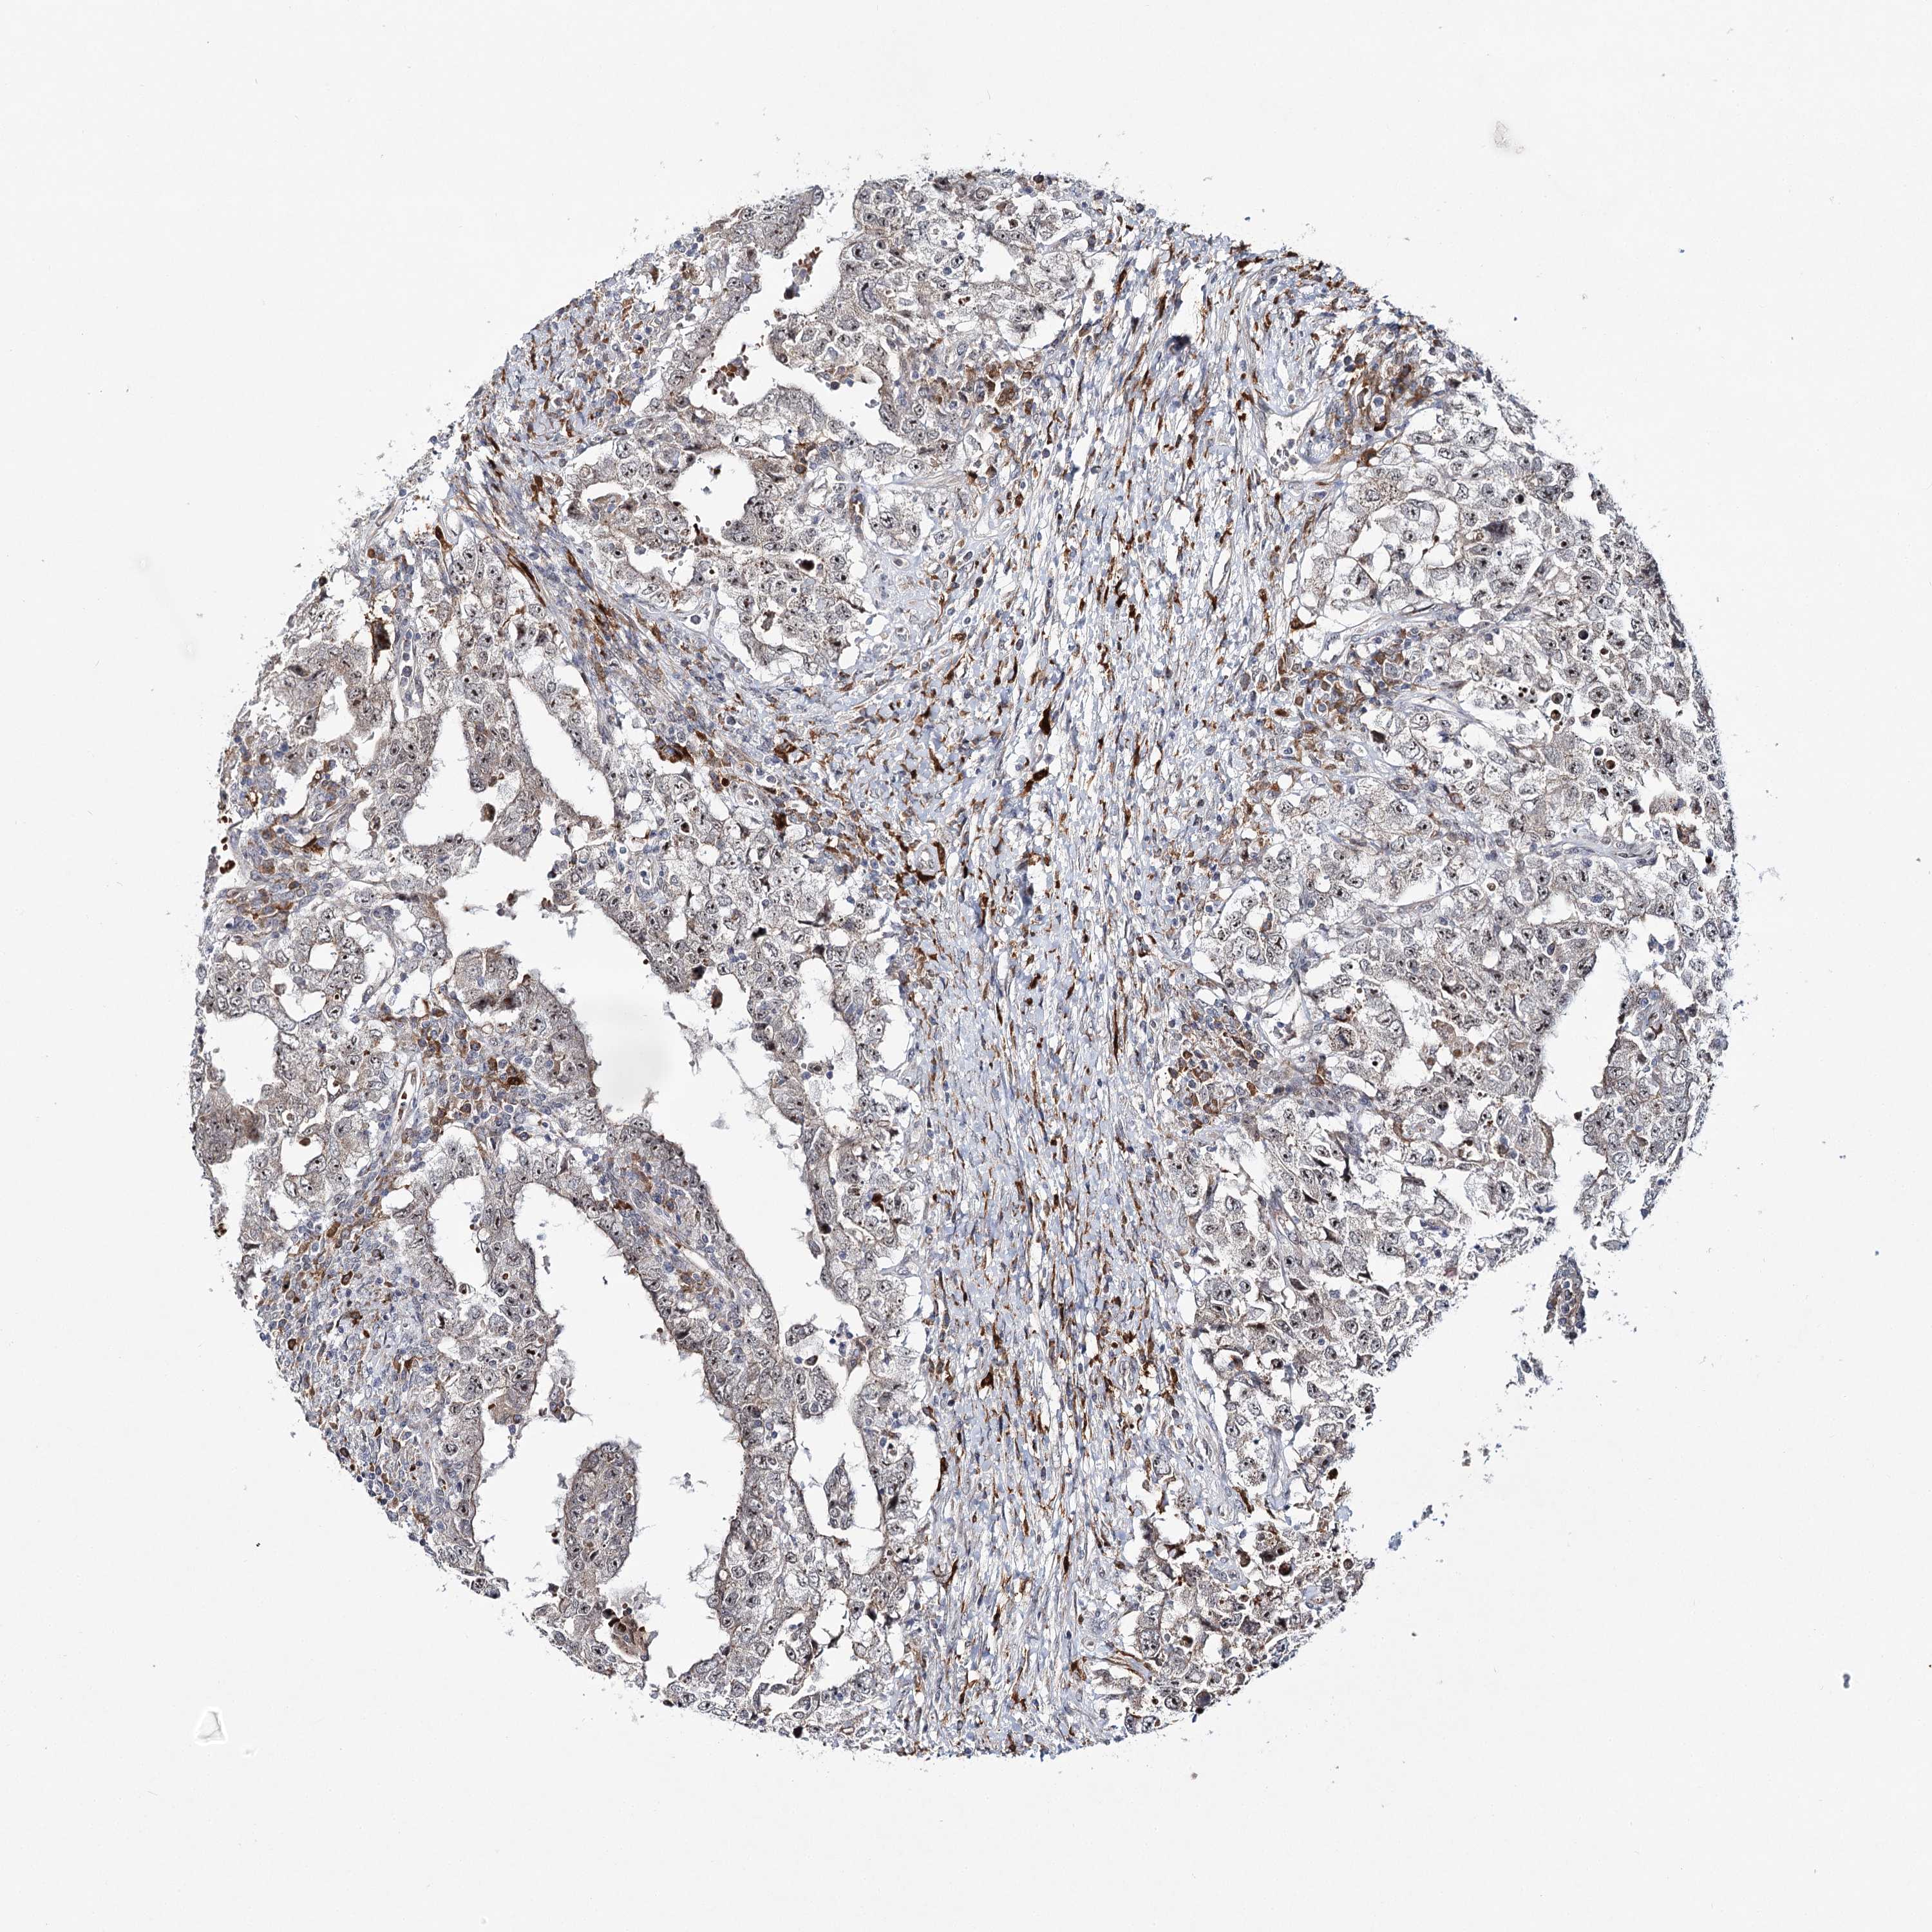

TESTIS CANCER - Protein expressioni

A mouse-over function shows sample information and annotation data. Click on an image to view it in a full screen mode. Samples can be filtered based on level of antibody staining by selecting one or several of the following categories: high, medium, low and not detected. The assay and annotation is described here.

Note that samples used for immunohistochemistry by the Human Protein Atlas do not correspond to samples in the TCGA dataset.

Antibody stainingi

Antibody staining in the annotated cell types in the current human tissue is reported as not detected, low, medium, or high, based on conventional immunohistochemistry profiling in selected tissues. This score is based on the combination of the staining intensity and fraction of stained cells.

Each image is clickable and will lead to virtual microscopy that enables deeper exploration of all samples and also displays staining intensity scores, fraction scores and subcellular localization as well as patient and tissue information for each sample.

Antibody HPA037796

Carcinoma, Embryonal, NOS

Seminoma, NOS

Urothelial carcinoma, High grade